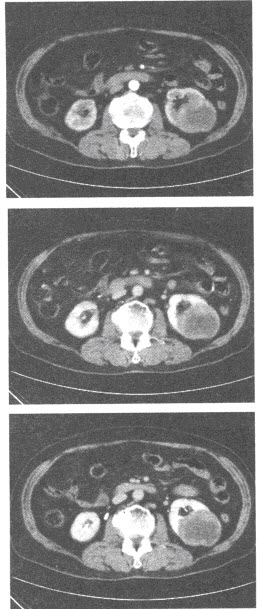

患者30岁,女性,右上腹持续性痛,腹胀,胸闷,食欲减退,消瘦。实验室检查,甲胎蛋白血清AFP试验阳性血清碱性磷酸酶(ALP)增高,CT示肝右前叶病灶。

(单选题)分析图像,结合病史,最可能的诊断是()

A:肝血管瘤破裂

B:肝血管平滑肌瘤破裂

C:肝癌并破裂

D:布-加综合征

E:以上都不是

第2题,共5个问题

(单选题)肝血管瘤的诊断标准错误的是()

A:平扫呈低密度,增强等密度,充填时间大于7分钟

B:强化区域进行性向病灶中央扩散

C:早期病灶边缘呈高密度强化

D:平扫呈低密度,增强后等密度,充填时间大于3分钟

E:延迟扫描病灶呈等密度充填

第3题,共5个问题

(单选题)下列哪项

不属于

我国肝癌协作病理组对肝癌的分类()

A:块状型

B:结节型

C:弥漫型

D:多灶型

E:小癌型